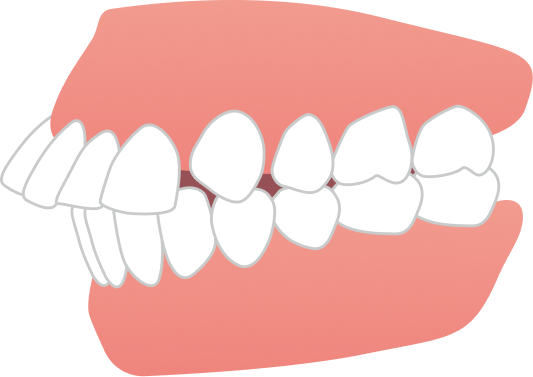

こちらの症例は20代女性の患者さまで、「下の前歯が1本前に出ていること」や「右上の前歯が出て見えること」を気にされて来院されました。

BEFORE